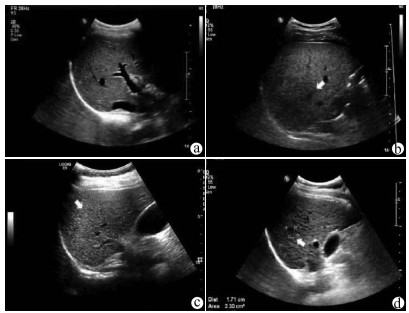

肝病超声诊断指南

中华医学会超声医学分会, 中国研究型医院学会肿瘤介入专业委员会, 国家卫生和健康委员会能力建设和继续教育中心超声医学专家委员会

2021, 37(8): 1770-1785. DOI: 10.3969/j.issn.1001-5256.2021.08.007

摘要(3138) HTML (6640) PDF (9311KB)(810)

超声检查无创、实时、价廉,无辐射、便于反复进行,是最常用的肝脏影像学检查方法。近年来,超声检查新技术如超声造影、弹性成像发展迅速,可有效鉴别肝内占位性病变性质、评估肝纤维化和门静脉高压程度以及监测肝病治疗效果,在临床肝病及其介入治疗中发挥重要诊断价值。本指南规范了肝病多模态超声技术(灰阶超声、彩色多普勒超声、超声造影、弹性超声)检查的仪器调置、患者准备及医生检查方法;对肝脏弥漫性病变(炎性病变、纤维化、硬化)、多种占位性病变及肝病介入操作的多模态超声技术诊断标准进行了定义和规范,同时推荐了超声监测周期及肝脏疾病超声诊断报告书写规范。